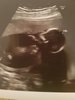

Fanka BB :)

Nie wiem czy Cię to pocieszy ale mnie po transferze bolał brzuch, jajnik a nawet cycusie. Szukałam plamienia implantacyjnego i nie było, a podobno czasem jest. Jesteśmy na lekach i chyba nie ma co interpretować jeszcze objawów. Poczekaj na betę to się wyjaśni. I się nie stresuj!Wierze ze to nie samowite doznanie.. Niech to bedzie piekna historia na kolejne 8.5 miesiecyja mam objawy na okres boj jajnikow coraz gorszy z dnia na dzien... I zarodek w 3 dobie podany.